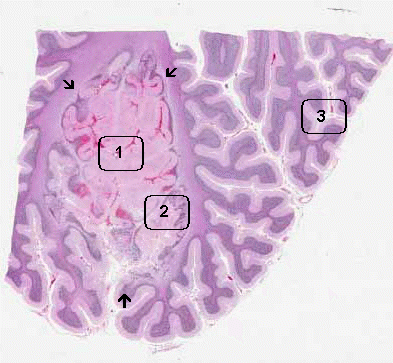

Gross Pathology: This image is taken from one of the infarcts in the cerebellum. There is an oval, darker lesion (L) involving the cerebellar folia. The cut surface of this area seems to be more irregular than the surround tissue. This area was submitted for microscopic examination and yielded the current slide. There are several much smaller dark areas  (arrows).

Histologic Highlights of this Case:

• The lesion is outlined by the white arrows. On the panoramic view, the lesion is a pale, pink, necrotic lesion that roughly follow the anatomy of the cerebellar folia. The center of the lesion has totally lost hematoxylin staining which is common feature of necrotic tissue. The necrotic tissue, however, still have the "ghost" structure of the folia.

• On higher magnification (Area A), there is no hematoxylin staining in the nuclei which is a classic feature of necrotic tissue.

• Compare Area A with the tissue at the edge of the infarct (Area 2) and those far away from the infarct (Area 3). Foamy histiocytic (macrophage) infiltration is present at the periphery but not the center of the infarct.

• There is no macrophages infiltrating this lesion.

• The smaller dark lesions identified on gross examination corresponds to small infarctions.

Gross Pathology: The fact that there is tissue disintegration and histiocytic infiltration at the periphery but not the center of the lesion indicate that this sample is obtained at an early stage of resolution and at least about 4 days after the onset of the infarction.